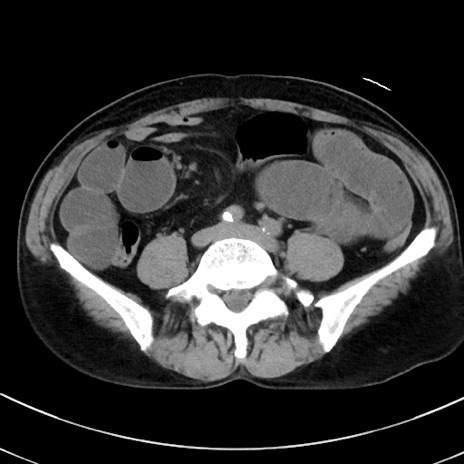

症例38(横断像)

冠状断像

【症例】70歳代 男性

【主訴】腹痛・嘔吐

【現病歴】昨晩より、嘔吐・腹痛あり。今朝になっても嘔吐あり。来院。

【既往歴】心臓バイパス手術、開腹胆摘、腸閉塞

【身体所見】BP 107/71mmHg、HR 116/min、腹部:平坦、軟、下腹部に軽度圧痛あり。反跳痛なし。

【データ】WBC 15100、CRP 0.32